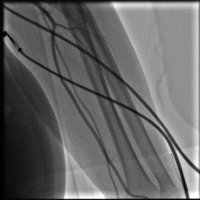

İyileşmeyen ayak yaraları ile kliniğimize refere edilen hastanın MR sonucunda sol sfa Total olduğu görüldü. İşleme alınan hastanın tam tıkalı bacak damarı özel mikro kateter ve özel tellerle geçilerek balon işleminden sonra tam açıklık sağlandı..